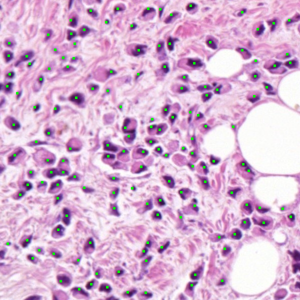

Dataset 3 consists of 50 annotated H&E-stained histological images from triple-negative breast cancer patients [74]. The images were acquired at 40× magnification using a Philips Ultra Fast Scanner (1.6RA) at the Curie Institute and contain a total of 4022 annotated cells.

Representative samples from the three datasets are shown in Fig. 1. In (a), the first frame of the synthetic video in Dataset 1 illustrates the strong illumination gradients produced by distance-dependent shading together with orientation-dependent interactions between vertex normals and the light direction. The H&E images in (b) and (c), also from Dataset 1, depict a mast cell infiltrate from a patient with non-alcoholic steatohepatitis and cirrhosis and, respectively, a sample from a patient with sclerosing polycystic adenosis of the parotid gland; the former consists primarily of purple nuclei, white cytoplasm, and pink extracellular tissue. Subfigures (d) and (e) show two examples from Dataset 2 accompanied by their ground-truth nuclei annotations, while (f) and (g) present a representative image from Dataset 3 together with its corresponding cell mask.

Figure 1: Samples from Datasets 1–3. (a) First frame of the 74-frame video in Dataset 1 (1770 × 880) with a superimposed red mesh. (b,c) H&E-stained tissue images from Dataset 1 (1000 × 750; 950 × 730). (d,e) Cell images from Dataset 2 (600 × 600) with nuclei annotations. (f,g) Image from Dataset 3 (512 × 512) with annotation.